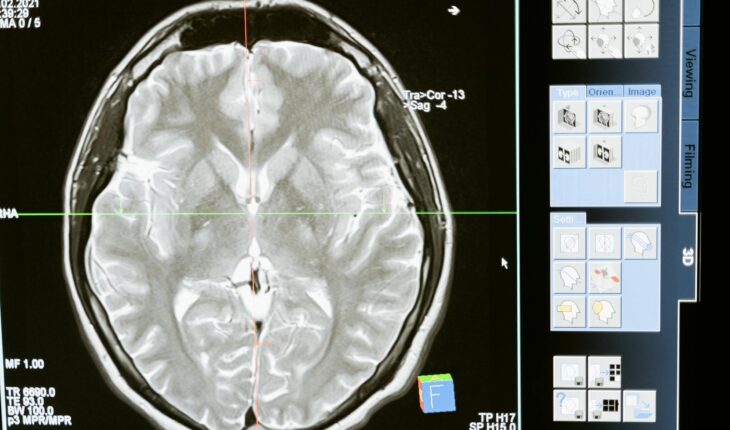

À l’arrivée aux urgences, le médecin de garde évalue avec précision le niveau de conscience et la force musculaire globale. L’investigation repose ensuite sur l’imagerie médicale afin de déterminer la nature de la lésion neurologique. Le scanner crânien identifie l’hémorragie avec une grande fiabilité. L’imagerie par résonance magnétique (IRM) excelle dans la détection précoce des zones ischémiées. L’angiographie met en évidence les occlusions artérielles. En parallèle, des analyses sanguines recherchent des troubles de la coagulation ou des infections sous-jacentes. L’électrocardiogramme et l’échocardiographie complètent le bilan pour évaluer le risque cardiaque.